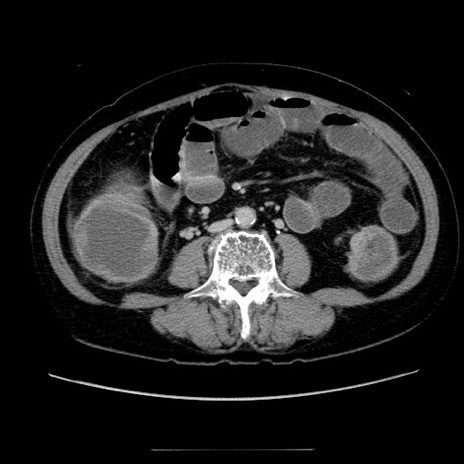

冠状断像

【症例】70歳代女性

【主訴】お腹が張る

【現病歴】1週間くらい前から腹部膨満の自覚あり。昨日夜から増悪したため、本日救急外来受診。

【身体所見】意識清明、BT 36.5℃、BP 165/106mmHg、HR 80bpm、SpO2 98%、腹部:膨満、軟、自発痛・圧痛なし、触診にて不快感あり、腸蠕動音:減弱

【データ】WBC 12600、CRP 1.04